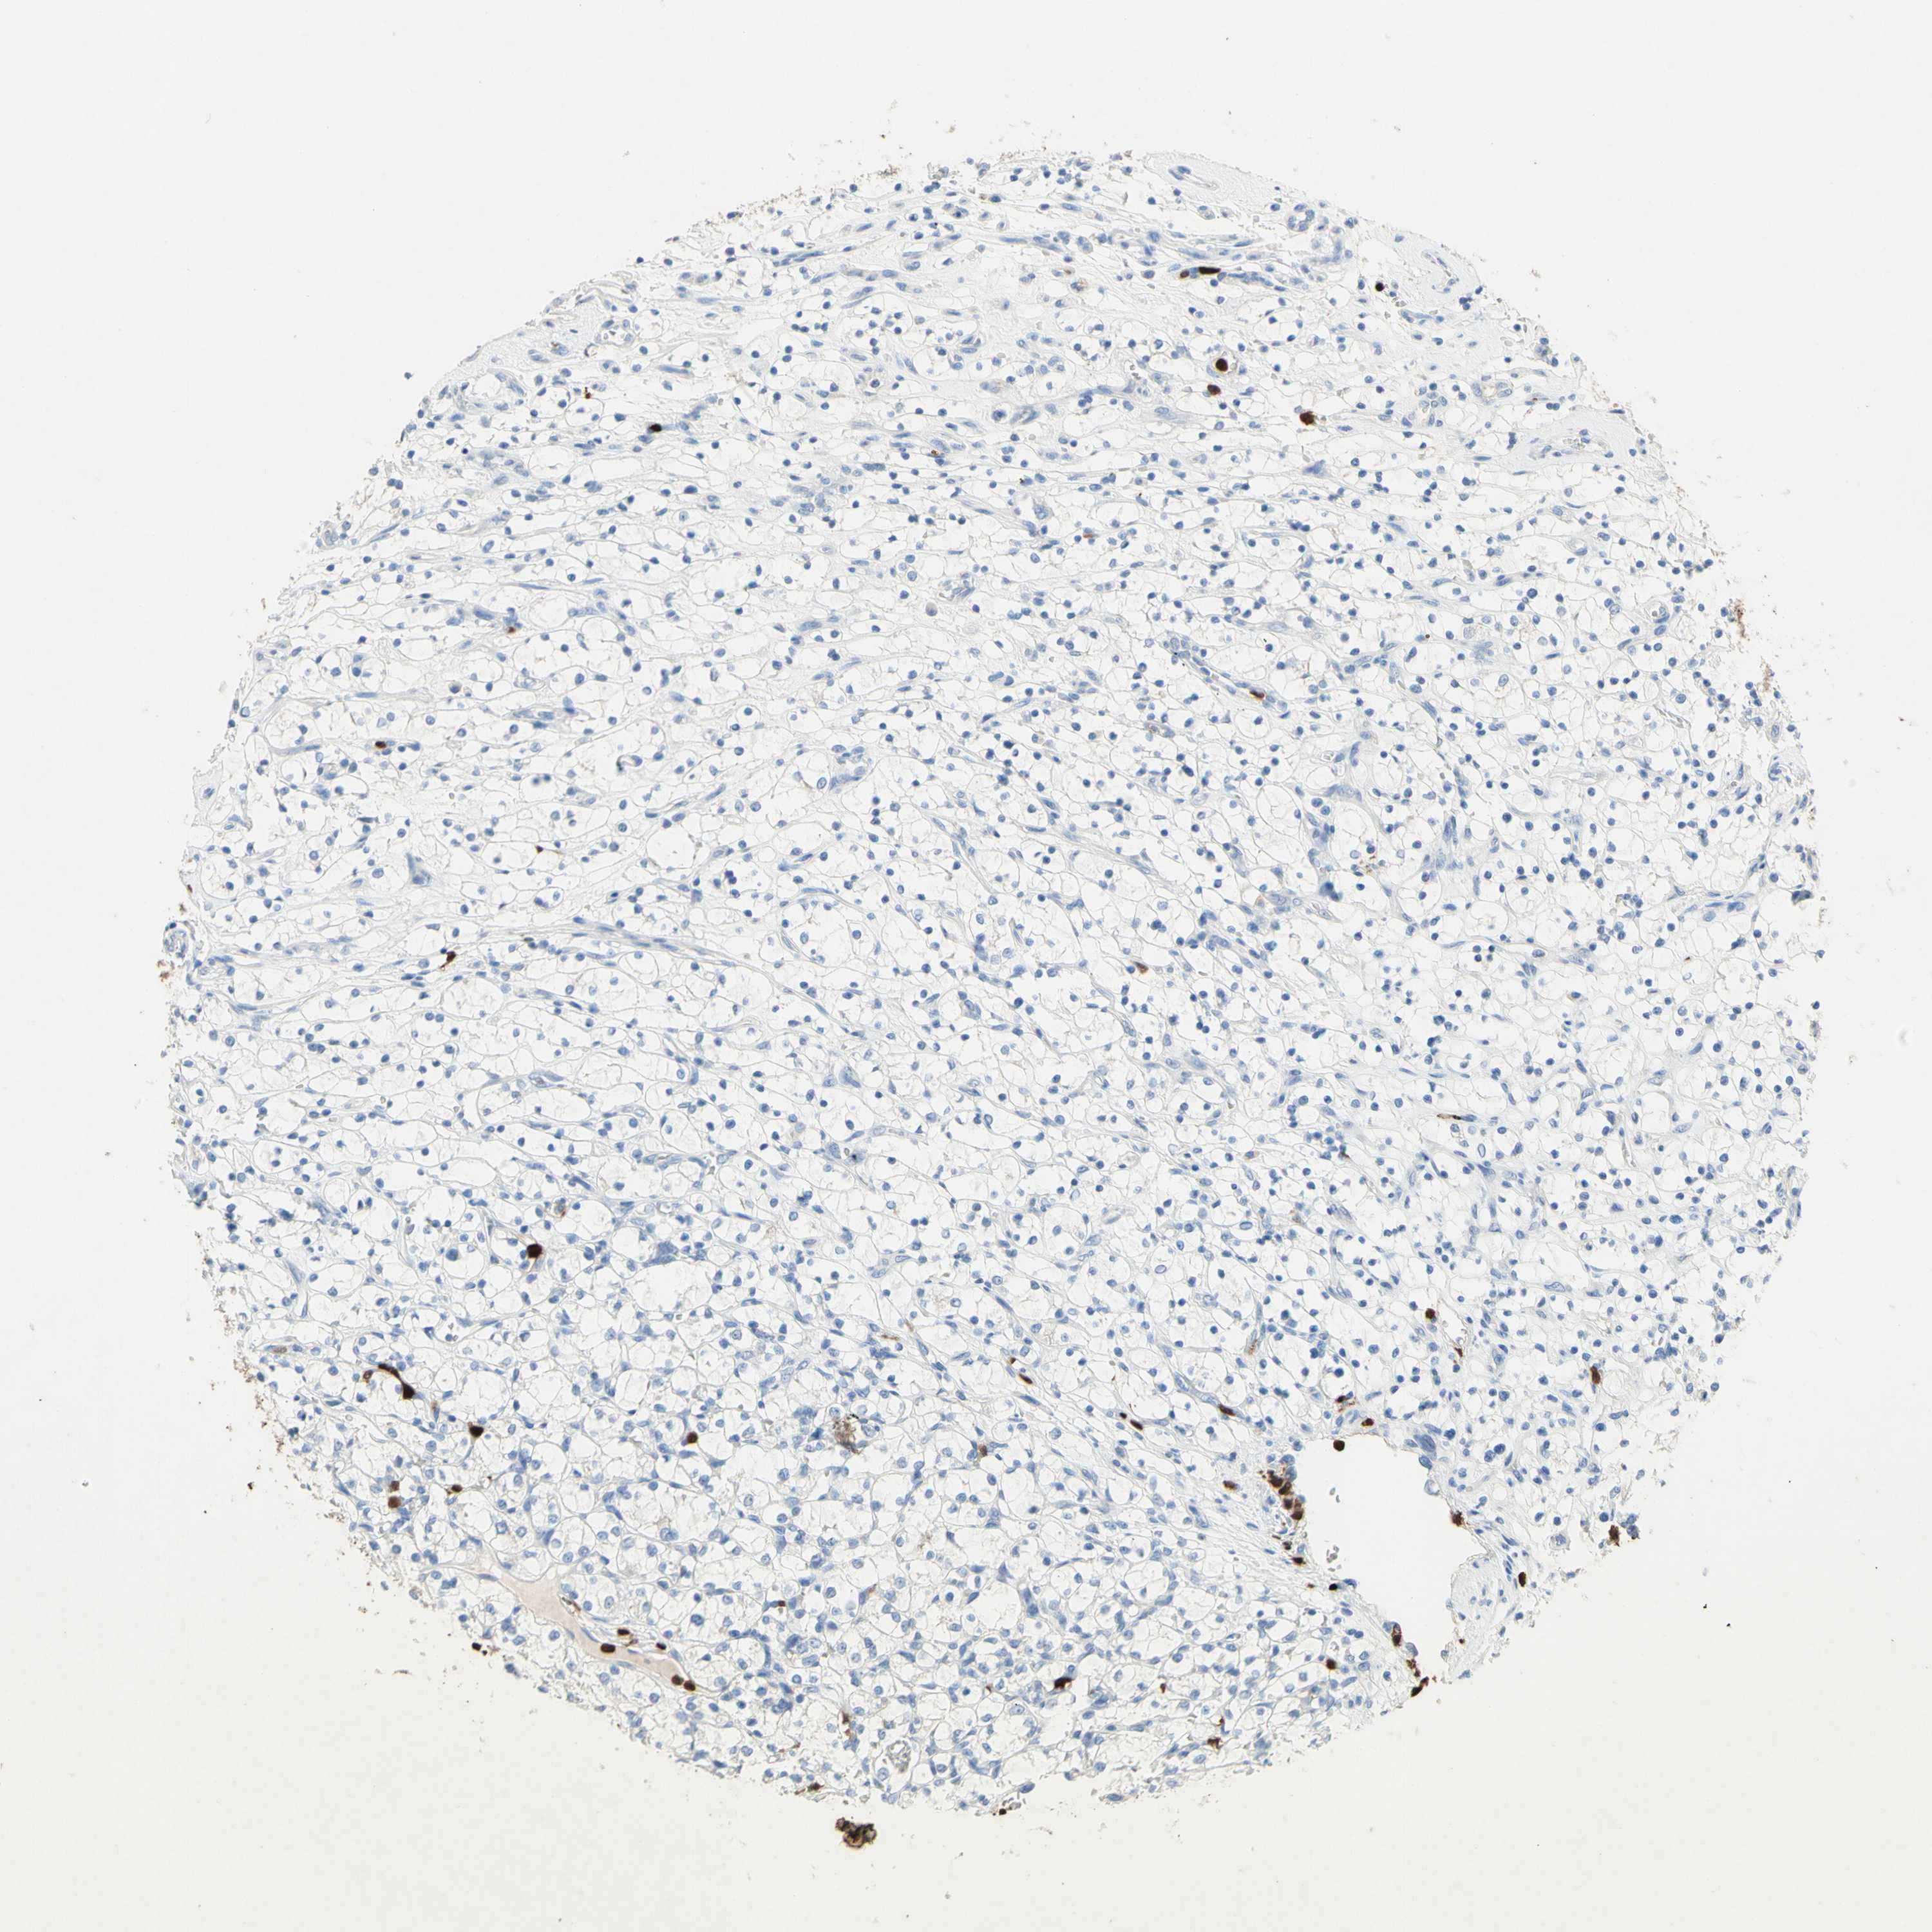

KIDNEY RENAL CLEAR CELL CARCINOMA (VALIDATION) - Interactive survival scatter ploti

The Survival Scatter plot shows the clinical status (i.e. dead or alive) for all individuals in the patient cohort, based on the same data that underlies the corresponding Kaplan-Meier plots. Patients that are alive at last time for follow-up are shown in blue and patients who have died during the study are shown in red.

The x-axis shows the expression levels (FPKM) of the investigated gene in the tumor tissue at the time of diagnosis. The y-axis shows the follow-up time after diagnosis (years). Both axes are complimented with kernel density curves demonstrating the data density over the axes. The top density plot shows the expression levels (FPKM) distribution among dead (red) and alive patients (blue). The right density plot shows the data density of the survived years of dead patients with high and low expression levels respectively, stratified using the cutoff indicated by the vertical dashed line through the Survival Scatter plot. This cutoff is automatically defined based on the FPKM cutoff that minimizes the p-score. The cutoff can be changed by dragging the vertical line or by entering a cutoff value in the square labeled "Current cut-off".

Under the Survival Scatter plot the p-score landscape (black curve; left axis) is shown together with dead median separation (red curve; right axis). Dead median separation is the difference in median mRNA expression between patients who have died with high and low expression, respectively. It is calculated as follows: median FPKM expression of dead patients with high expression - median FPKM expression of dead patients with low expression. This is intended to aid the user in visually exploring custom cutoffs and the associated p-scores and dead median separation.

Individual patient data is displayed and can be filtered by clicking on one or more of the category buttons on the top of the page. Categories describing expression level and patient information include: high, low, alive, dead, female, male and tumor stages. The scale of the x-axis can be toggled between linear and log-scale by clicking on the "x log" button. Mouse-over function shows TCGA ID, patient information and mRNA expression (FPKM) for each patient.

& Survival analysisi

Kaplan-Meier plots summarize results from analysis of correlation between mRNA expression level and patient survival. Patients were divided based on level of expression into one of the two groups "low" (under cut off) or "high" (over cut off). X-axis shows time for survival (years) and y-axis shows the probability of survival, where 1.0 corresponds to 100 percent.

NFKBIZ is not prognostic in Kidney Renal Clear Cell Carcinoma (validation)

Best expression cut offi

Based on the FPKM value of each gene, patients were classified into two groups and association between prognosis (survival) and gene expression (FPKM) was examined. The best expression cut-off refers the FPKM value that yields maximal difference with regard to survival between the two groups at the lowest log-rank P-value. Best expression cut-off was selected based on survival analysis .

When clicking on this number, the vertical dashed line indicating cut-off, the interactive survival plot, and the Kaplan-Meier curve will be adjusted to show results based on the best expression cut-off.

: 7.66

Average pTPM 20.0

Number of samples 100